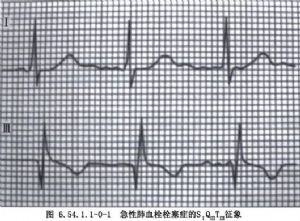

急性肺动脉栓塞(简称肺栓塞pulmonarpulmonary embolism)是指肺动脉或其分支管腔内突然机械性阻塞。阻塞物通常是血栓栓子,90%来源于下肢深静脉内的血栓而后脱落所致。由于肺动脉的机械性阻塞,加以栓子而致的反射性及液递因素引起血管痉挛,肺血管床阻力急骤升高,右心室后负荷突然增加。如肺动脉阻塞范围超过50%(大块肺栓塞),将出现明显血流动力学障碍:右室及肺动脉平均压和中心静脉压上升,而肺毛细血管楔压下降,心排出量锐减,心率增快,血压下降,产生一种特殊类型的休克-阻塞性心源性休克。加以栓塞肺的死腔通气以及未栓塞肺的通气血流比例失调,导致中至重度低氧血症,约10%~30%的病人可在1h内死亡,在欧美已居为死亡原因第三位的疾病。我国尚无有关发病率的确切统计,但有资料表明其发生率有较快增长的趋势。根据栓子大小的不同,所造成的血流动力学改变及临床症状差异甚大,自轻度的气急、胸痛,或呼吸困难、虚脱、休克直至心跳骤停。因此其治疗方法亦迥然不同,自一般的对症处理,循环呼吸支持,或抗凝治疗、溶栓治疗,直至紧急体外循环或常温阻断循环下行肺动脉取栓手术。大部分病人适用溶栓疗法,只有少数(约占病例总数的5%左右)病情紧迫,循环状态难以维持,时间已不允许等待溶栓药物产生作用,或者已经发生了心搏停止的病人,须做紧急手术处理。在未发生心搏停止之前与发生以后做手术取栓子的病死率分别为10%~30%和60%~70%,在未出现休克以前与在休克状态下做手术取栓子的病死率分别为17%和42%,可见有关本病治疗的问题,主要在于适时又恰当的手术决策(图6.54.1.1-0-1~6.54.1.1-0-4)。